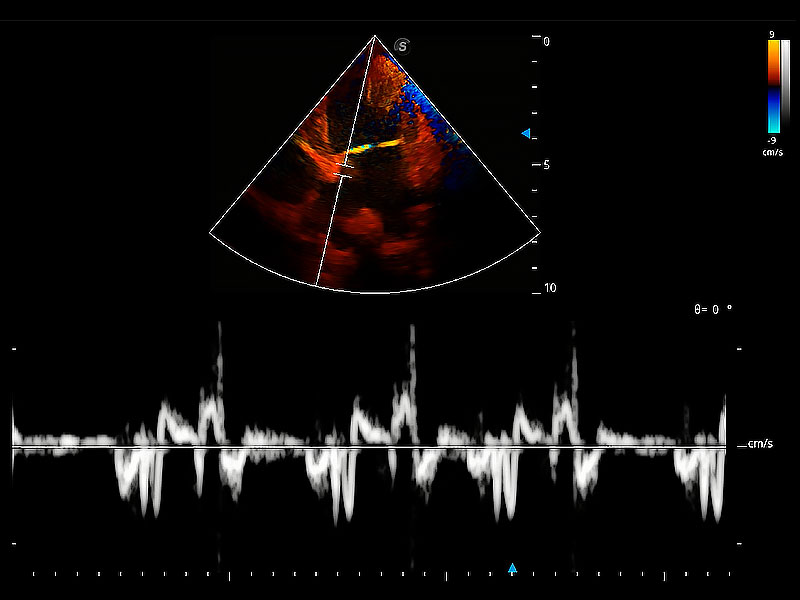

ProPet 80 配備了豐富的心臟探頭群、先進(jìn)的成像技術(shù)和專業(yè)的心臟測(cè)量工具,可幫助動(dòng)物醫(yī)生為不同體型和生理結(jié)構(gòu)的動(dòng)物提供心臟和心肌功能的全面評(píng)估。

實(shí)時(shí)用顏色表示心肌組織運(yùn)動(dòng),觀察和定量組織的運(yùn)動(dòng)情況,對(duì)快速檢測(cè)與評(píng)估心肌的灌注和活性、電傳導(dǎo)及心肌收縮和舒張功能等均能提供重要的診斷信息。

通過(guò)360度任意調(diào)節(jié)3條M型取樣線,在同一心動(dòng)周期上觀察心臟不同位置的運(yùn)動(dòng)曲線,得到準(zhǔn)確的心功能測(cè)量數(shù)據(jù),有效評(píng)估心肌運(yùn)動(dòng)及左心室功能。